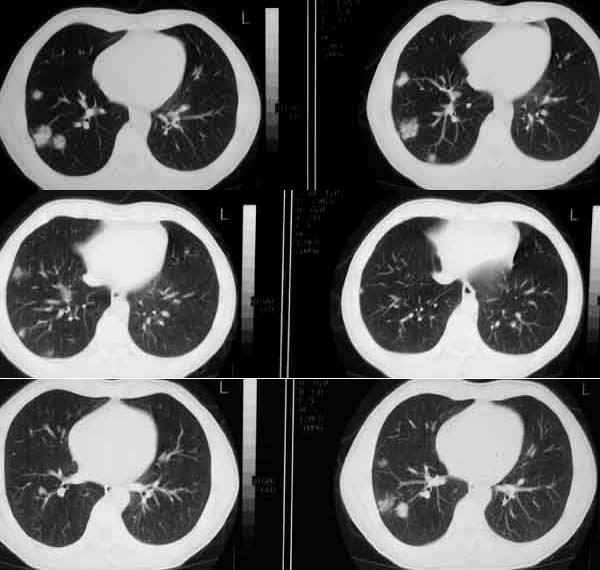

(1)发生部位:炎性假瘤可发生在两肺的任何部位,但多位于肺的表浅部位,邻近胸膜处或者靠近叶间裂。可以跨叶生长,原因可能是跨叶浸润的炎症使得假瘤跨叶融合的结果。

(2)假瘤形态:炎性假瘤的形态不一,可呈圆形.椭圆形或类圆形,也可呈驼峰状或不规则图形。

(3)假瘤大小:多数假瘤的直径在2-4cm,也可大于5cm,少数甚至大于10cm.

(4)假瘤密度:炎性假瘤一般为中等密度,密度均匀。而脓性炎症形成的假瘤则有时可见小空洞。空洞可以单发也可多发。少数瘤体切开时可见脓性物。

(5)假瘤边缘:

①有假无假性包膜者边缘清楚。有的由于肿块不规则可表现分叶状。

② 无假性包膜者,假瘤周围有纤维化和多种细胞成分侵润,表现为片状、边缘模糊的团块状影。或有轻度的渗出性病变,边缘模糊,以组织细胞围增生型多见。有的假瘤周围还可以出现类似周围型肺癌的放射冠状表现。

(6)邻近改变:位于肺周边部的假瘤,其邻近胸膜可见局限性粘连增厚。位于近肺门区的假瘤,偶可阻塞支气管,形成肺叶不张而将假瘤包裹,甚似中央性肺癌,但不出现肺门或纵膈淋巴结肿大。

(7)王学成等指出肺炎性假瘤胸腔无胸水出现,有利于与肺癌、肺结核鉴别。

(8)动态观察:假瘤可在数年之内无明显增大,当并发急性炎症时,可以使“瘤”体增大,少数炎症可以发生癌变。

(9)增强检查大多数肿块可见较显著的均匀强化,少数仅见肿块周围部强化甚或肿块不强化,这与肿块的组织结构成分,特别是血管成分有关。少数病人可见同侧肺门及纵隔淋巴结肿大,其直径常小于1.5cm.